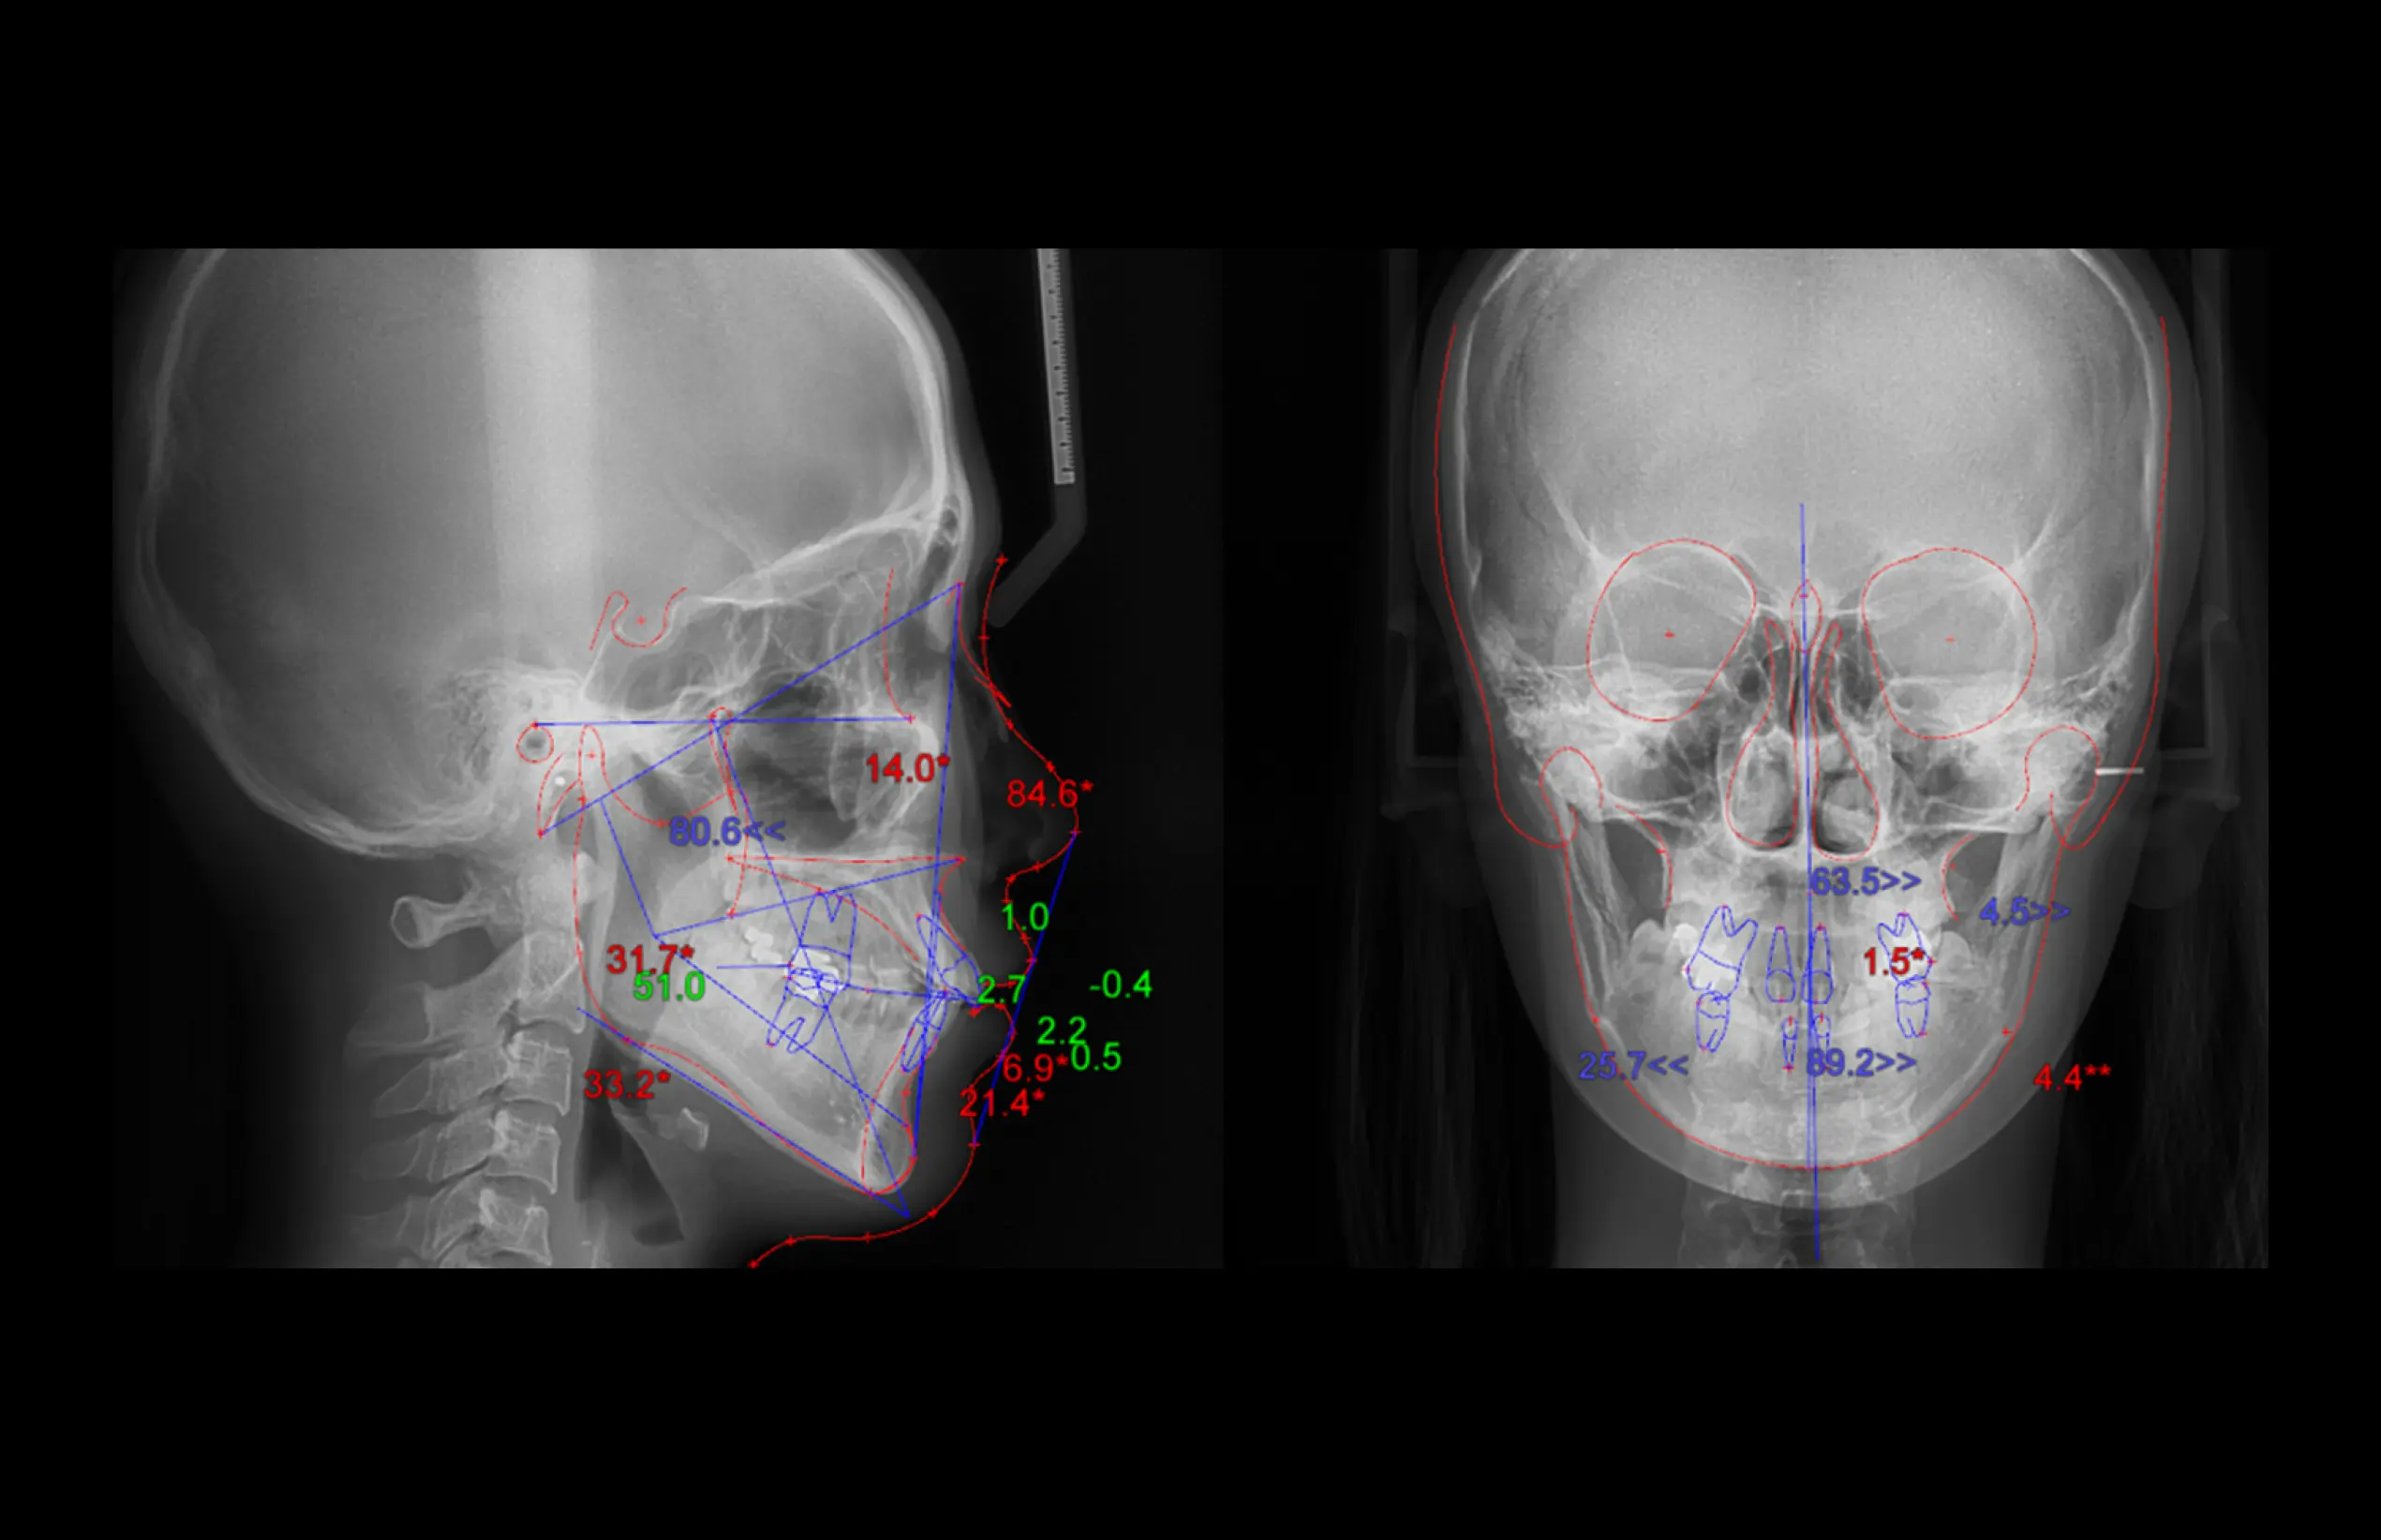

MDSDental Solution

더보기 오토 트레이싱

·환자의 X-ray (측면 & 정면)에서의 디지털

트레이싱

·클릭 한번으로 빠르고 정확한 AI기반의 자동

트레이싱